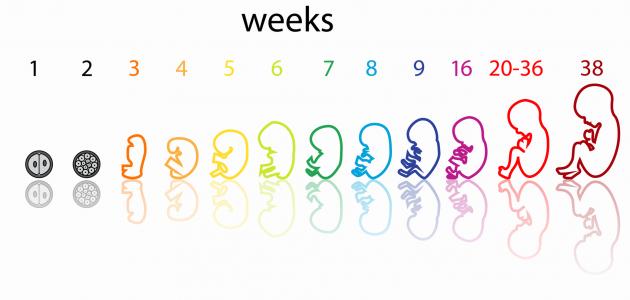

يستمر الحمل (بالإنجليزية: Pregnancy) النموذجي 40 أسبوعًا تقريبًا؛ تبدأ من اليوم الأول من آخر دورة شهرية حتى الولادة، وتُقسم لثلاث مراحل أو فصول ينمو ويتطوّر فيها الجنين بطريقة معينة،[١] فيبدأ الفصل أو الثلث الأول من الأسبوع الأول من الحمل وينتهي بانتهاء الأسبوع الثالث عشر، ويتبعه الثلث الثاني الذي يبدأ من الأسبوع الرابع عشر ويستمر إلى حوالي الأسبوع السادس والعشرين، ثمّ ينتهي بالثلث الثالث الذي يمتدّ حتى الولادة أي الأسبوع الأربعين،[٢] وفيما يأتي بيان لهذه الفصول بشيء من التفصيل:

فيما يأتي بيان مراحل تكون الجنين بالأسابيع الخاصة بالثلث الأول من الحمل:

- الأسبوع الأول: وفيه يستعد الجسم للحمل من خلال زيادة سمك بطانة الرحم (بالإنجليزية: Uterus) ليتمكن من إيواء البويضة المخصبة وتغذيتها بمجرّد انغراسها في بطانته، لذلك لا يُعد هذا الأسبوع جزءًا رسميًا من الحمل، ولكن تسهيلًا لحساب عمر الحمل فإنّ الطبيب يتتبع الحمل وموعد الولادة اعتمادًا على اليوم الأول من آخر دورة شهرية للمرأة.[٢]

- الأسبوع الثاني: يحدث التبويض (بالإنجليزية: Ovulation) بداية هذا الأسبوع، وتُخصّب البويضة بعد تقريبًا 12-24 ساعة من قبل الحيوان المنوي، وبمجرّد تخصيبها تبدأ بالانقسام إلى خلايا متعددة من خلال سلسلةٍ من العمليات المعقدة، ويكون ذلك أثناء انتقالها إلى أسفل قناة فالوب، ثمّ تدخل الرحم وتبدأ بالانغراس في بطانته.[٣]

- الأسبوع الثالث: وفيه تنزرع أو تنغرس البويضة المخصبة في بطانة الرحم الغنية بالمواد الغذائية، وتسمّى حينئذٍ الكيسة الأريمية أو الكبسولة البلاستوليّة (بالإنجليزيّة: Blastocyst)، إذ تكون ككرة صغيرة جدًا تتكون من مئات الخلايا التي تتكاثر بسرعة وتتطور إلى جنين، ولإيقاف المبيضين عن إطلاق المزيد من البويضات لاحقًا تُنتج هذه الخلايا هرمون الحمل (بالإنجليزية: Pregnancy hormone) المعروف علميًا بهرمون موجهة الغدد التناسلية الميشمائية البشرية واختصارًا hCG.[٣]

- الأسبوع الرابع: يكون الجنين الآن قد التصق بجدار الرحم، وتستمرّ الخلايا بالانقسام التي ستُكوّن أعضاؤه في الفترة القريبة، وقد يمكن رؤيته بالموجات فوق الصوتية لكن يكون بحجمٍ أصغر من حبة الأرز، ويبدأ هنا تشكّل الكيس الأمنيوسي أو ما يُعرف بكيس الحمل (بالإنجليزية: Amniotic sac) وهو أشبه ما يكون بوسادة مملوءة بسائل تحيط بالجنين وتحميه أثناء نموّه، ويكون الكيس متصلًا بالكيس المحّي أو الحويصلة السرية (بالإنجليزية: Yolk sac) ليُمدّ الجنين بالمواد الغذائية خلال الأسابيع الأولى.[٢]

- الأسبوع الخامس: قد يكون من الممكن ملاحظة نبض قلب الجنين خلال الموجات فوق الصوتية، لكن لا يمكن سماعه في هذه المرحلة، وباستمرار نموّ الجنين تبدأ الأم بالشعور بأولى أعراض الحمل كألم الثدي، وغثيان الصباح والحاجة المتكررة للتبول، ومن الجدير بالذكر أنّ الجنين في هذه المرحلة يتكون من ثلاث طبقات متميزة تتطوّر مع مرور الوقت لتشكّل فيما بعد أعضاءه وأنسجته، وهذه الطبقات هي:[٢][٤]

- الأسبوع السادس: في نهاية الأسبوع السادس سوف يكون حجم الجنين قد تضاعف ثلاث مرات، وستتشكل نصفا الكرة الدماغية، كما يمكن الآن تسجيل موجات الدماغ، أمّا عن القلب فينبض بانتظام بمعدل 150 نبضة تقريبًا في الدقيقة أي بما يعادل ضعف متوسط معدل ضربات قلب البالغين، لكن لا يزال النبض ضعيفًا لذلك لا يمكن سماعه بسماعة الطبيب.[٤]

- الأسبوع السابع: ينمو دماغ الجنين في هذه المرحلة بشكل أكثر تعقيدًا، وقد يمكن للطبيب رؤيته بوضوح داخل الجمجمة الشفافة، وفي الواقع تنمو الخلايا العصبية في هذه المرحلة بمعدّل مذهلٍ قد يصل إلى 100,000 خلية في الدقيقة، إضافةً إلى ذلك تتطوّر في هذا الأسبوع ملامح وجه مميزة للجنين، إذ تدلّ البقع الداكنة على مكان العيون وفتحات الأنف، كما يبدأ تشكّل جزء بسيط من الفم والأذنين أيضًا.[٤]

- الأسبوع الثامن: تحدث تطوّرات عديدة تتمثل بالآتي:[٥]

- +’الأسبوع التاسع:’ وفيه يكون القلب تقريبًا قد انقسم إلى أربع حجرات وجميع الأعضاء الأساسية للجنين في مكانها الصحيح إلى حدّ ما، وبنهاية هذا الأسبوع سيصبح حجمه بحجم حبة العنب إذ سيصل طوله حوالي 2.3 سنتيمترًا ووزنه حوالي 2 جرام، ومع اقتراب ذيل الجنين بالاختفاء سيبدو بشكل الإنسان أكثر، وستحدث التطورات الآتية لديه:[٦]

- الأسبوع العاشر: في الأسابيع الماضية كان الجنين في مرحلته الجنينية التي تتكون فيها الخلايا اللازمة لتشكل أعضائه الرئيسة وأطرافه ودماغه وجهازه العصبي، وسينتقل في هذا الأسبوع إلى مرحلة ينمو فيها بشكل واضح ومستمرّ إلى أن يصبح جاهزًا للخروج من الرحم، وفي هذا الأسبوع سينكمش الكيس المحي الذي كان يزود الجنين بالعناصر الغذائية قبل نمو المشيمة، ويُشار إلى بلوغ وزنه هنا حوالي 4 جرام، وطوله حوالي 3.1 من الرأس إلى الردف، بحيث يكون بحجم حبة الزيتون الأخضر تقريبًا، وستُلاحظ التطورات الآتية على الجنين:[٧]

- الأسبوع الثالث عشر: يصبح الجنين في هذا الأسبوع قادرًا على وضع إبهامه في فمه، ويومًا بعد يوم يبدو وجهه أكثر شبهًا بالإنسان، إذ تنتقل عيناه من جانبي رأسه إلى مقدمه وجهه، وقد تظهران بلون أزرق أو بنيّ أو أخضر، وتنتقل أذناه إلى مكانهما، وينمو جذعه بشكلٍ أسرع، كما يزداد طول ذراعيه ليتناسب أكثر مع جسمه.[٤]

مع بداية الثلث الثاني يكون حجم الجنين ما زال صغيرًا، ومن الجدير بالذكر أنّه بتخطي الشهور الثلاثة الأولى يقل خطر التعرض للإجهاض (بالإنجليزية: Miscarriage)، وتبدأ أعراض الحمل المبكرة التي عانت منها الحامل كالتعب وغثيان الصباح بالاختفاء، وقد تشعر بأنها أكثر نشاطًا فيصبح باستطاعتها ممارسة التمارين الرياضية بعد الرجوع لطبيبها لأخذ المشورة الطبية حول الرياضة المناسبة للحامل عامّةً ولحالتها الصحية خاصةً،[٣] وفيما يأتي بيان هذه المرحلة من الحمل بالتفصيل: